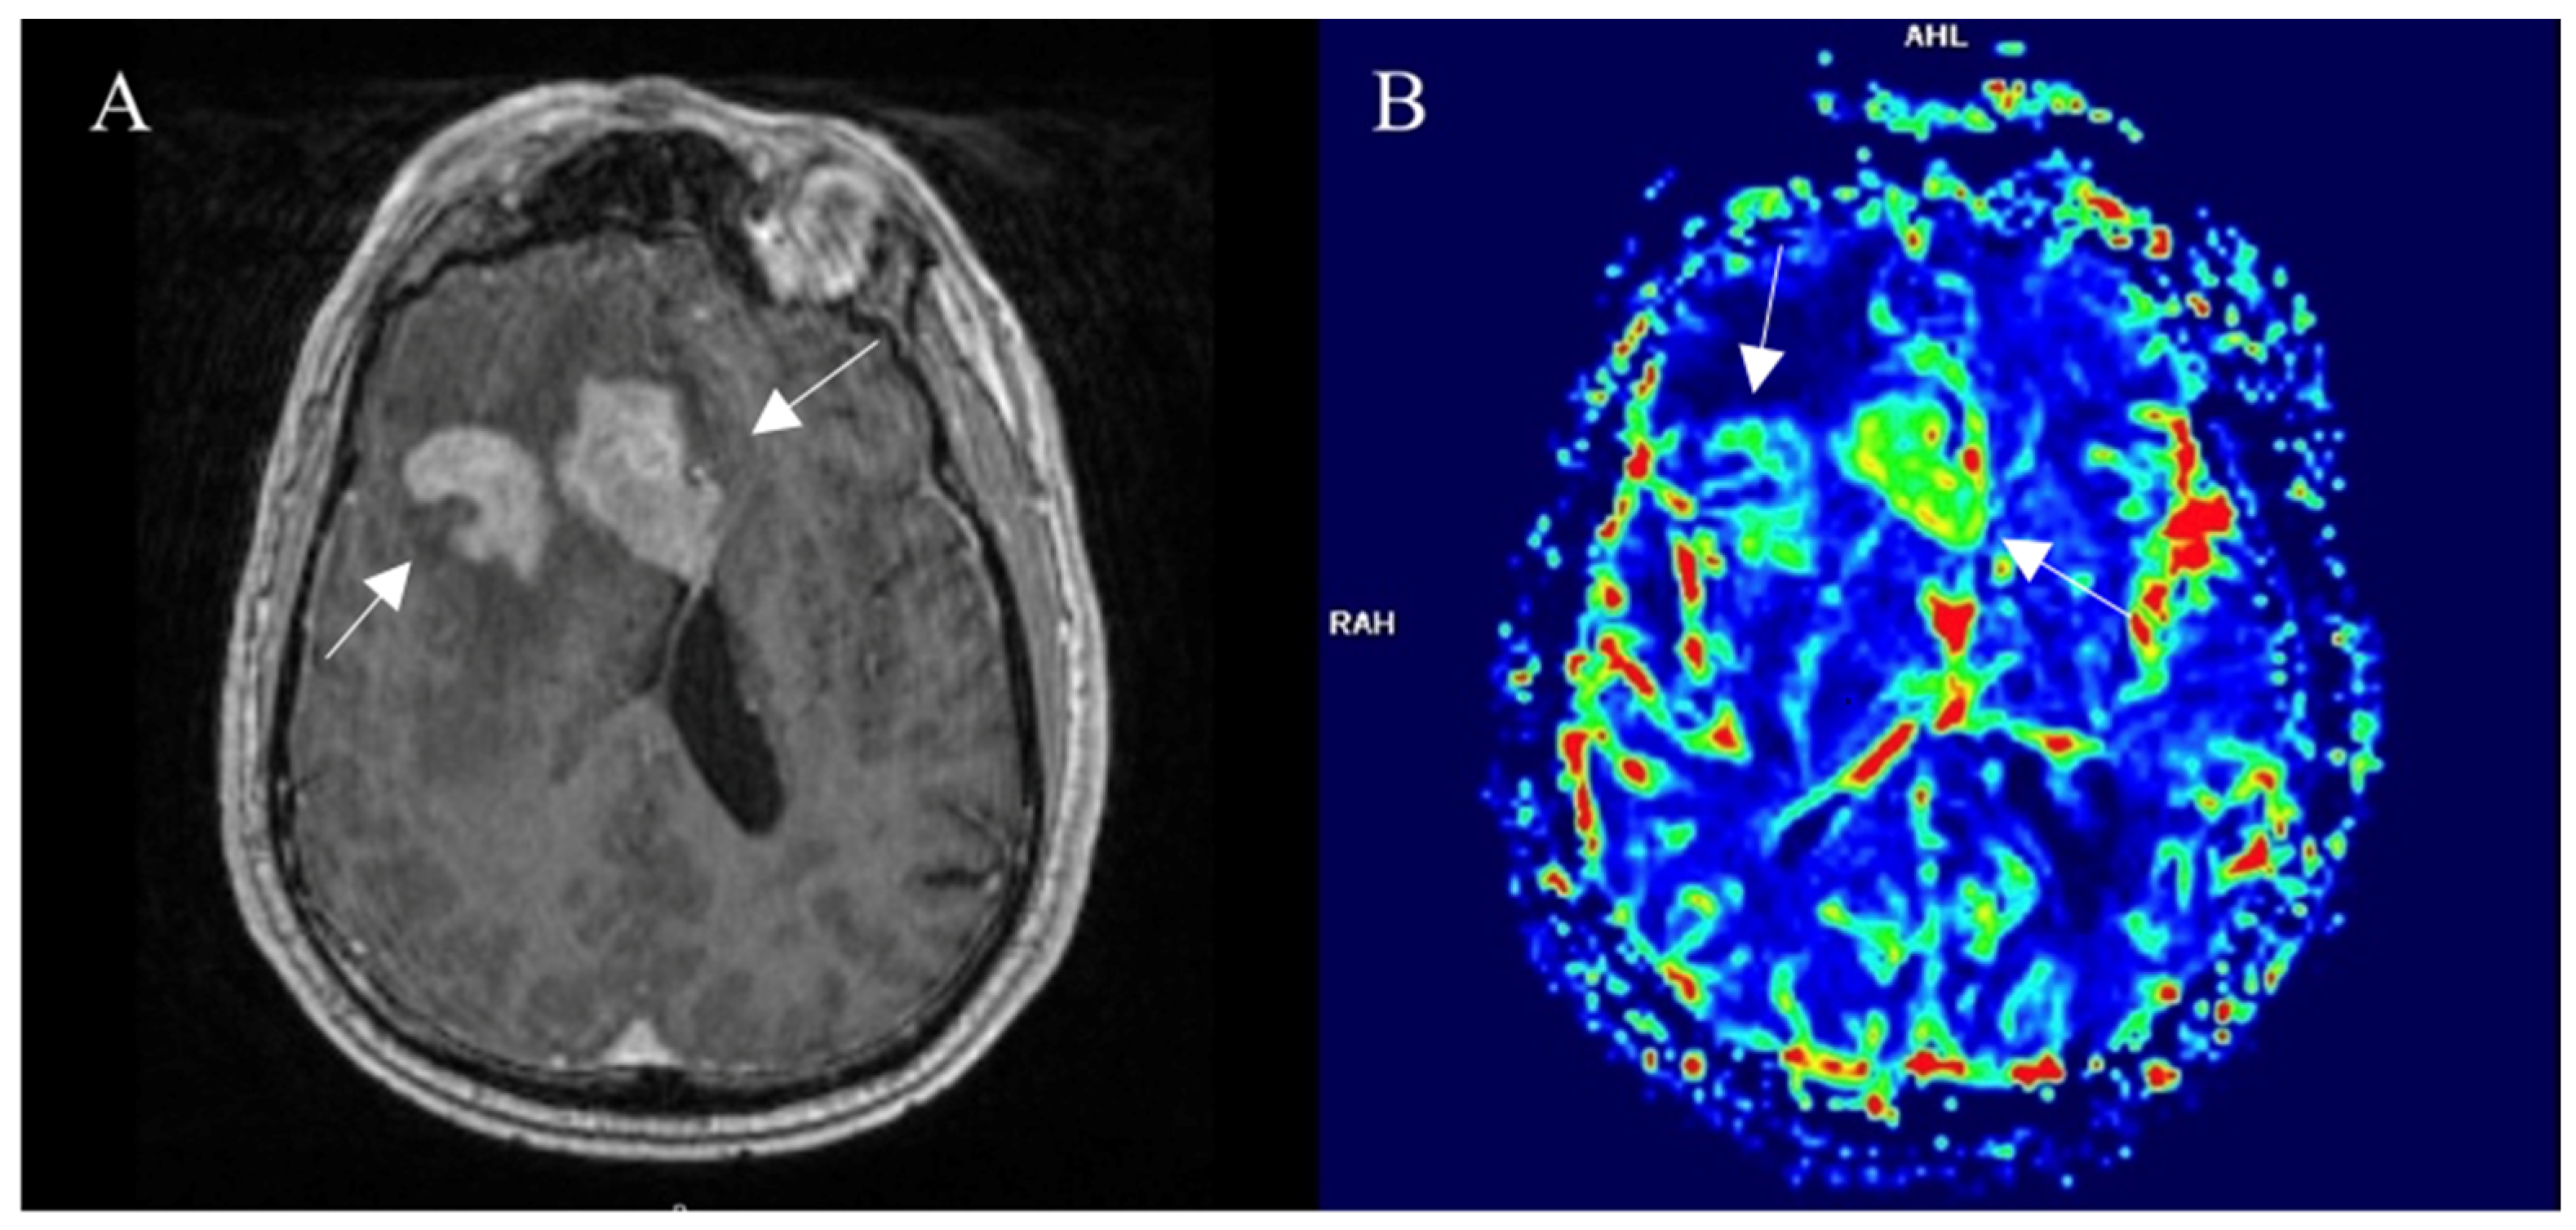

3.5.1. Positron Emission Tomography

3.5.2. SPECT